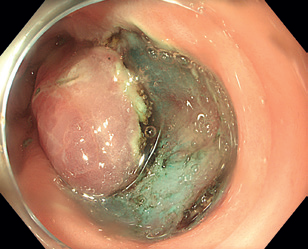

Obr. 3 Stopkatý polyp 0‑Ip zobrazený metodou Narrow Band Imaging.Endoskopická polypektomie (EPE) představuje základní a nejčastěji využívanou terapeutickou proceduru v oblasti gastrointestinální endoskopie. Princip EPE spočívá v naložení polypektomické kličky na stopku stopkatého polypu (0‑Ip), která je tvořena zdravou sliznicí a submukózou, následně je tato stopka přerušena kombinací mechanické síly při uzavření smyčky a elektrického koagulačního proudu (technika známá jako „hot snare“) (obr. 3–5). U rizikových polypů (šíře stopky nad 10 mm či velikost polypu nad 20 mm) se pro minimalizaci rizika krvácení doporučuje před resekcí stopku infiltrovat roztokem adrenalinu, popř. na stopku naložit endoklipy nebo použít odnímatelnou smyčku, známou též jako „endo­loop“, která po resekci polypu zůstává na stopce (obr. 6). EPE se často využívá i pro resekci malých plochých nebo přisedlých lézí (0‑IIa, 0‑Is) s průměrem ≤ 10 mm (obr. 7), a to obvykle pouze v mechanickém režimu bez využití elektrické koagulace (technika známá jako „cold snare“). Tato metoda snižuje riziko pozdějšího krvácení a vzniku koagulačního syndromu. „Resekce“ diminutivních lézí pomocí biop­tic­kých kleští, běžně používaná v minulosti, byla do značné míry opuštěna pro riziko inkompletní resekce a nahrazena právě „cold snare“ polypektomií. Klešťovou resekci je nadále možno použít jen u lézí do velikosti 3 mm. Použití elektrokoagulačních kleští („hot forceps”) se obecně nedoporučuje.